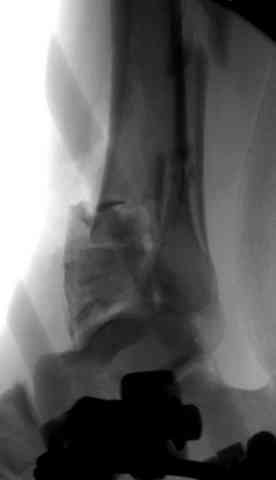

Снова приветствую вас, коллеги. К моменту вступления в обсуждение аксакалов, операция была, увы, выполнена(31.10.07.) Начали с доступа к наружной лодыжке, произвели ее фиксацию спицами, развернули кусок заднего края, наложили дистрактор, затем произвели дистракцию, фиксацию спицами дистального эпиметафиза б/бк,Рентгено-контроль. синтез наружной лодыжки 1/3пластиной. из двух коротких разрезов сформирован канал под медиальную тибиальную пластину LCP. Края ран ушиты без натяжения. Прочувствовать жесткость фиксации винтами с угловой стабильностью не удалось, поэтому дистрактор оставлен на энное время.

На представленных R-снимках не окончательный вид после остеосинтеза. Дистальная опора давила на стопу, пришлось ее сместить проксимально, в рез-те чего, она закрыла щель сустава, последние снимки не информативны.

Честно признаться тяжело на душе после такой операции,-было всё хорошо после первоначальной дистракции, хорошая редукция отломков, после остеосинтеза пластинами появилась подвывых стопы кнаружу, от пластини LCP никакой толку-дистальные винты в зоне излома и дистальный отломок не охвачен, проксимально всего один винт, дистальные винты из м/б кости проходят сквоз сустава и упирается в таранку, стопа в эквинусном положении.Если даже всё обойдется, этот сустав нормально не будет работат.